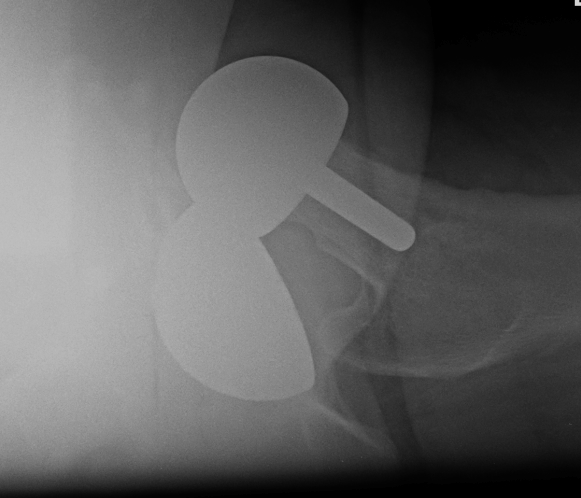

Birmingham hip resurfacing

Concept

Femur - removal of femoral head cartilage and resurfacing with metal

Acetabulum - standard technique

Bearing surface - metal on metal

Birmingham Resurfacing

Oversized head

Varus Femoral Component

Femoral head notching

Open Acetabular Component - may cause point loading and increased metal wear